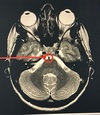

15

Q

A. Fat

B. Submandibular gland

C. Parotid gland

D.Sternocleidomastoid

A

C. Parotid